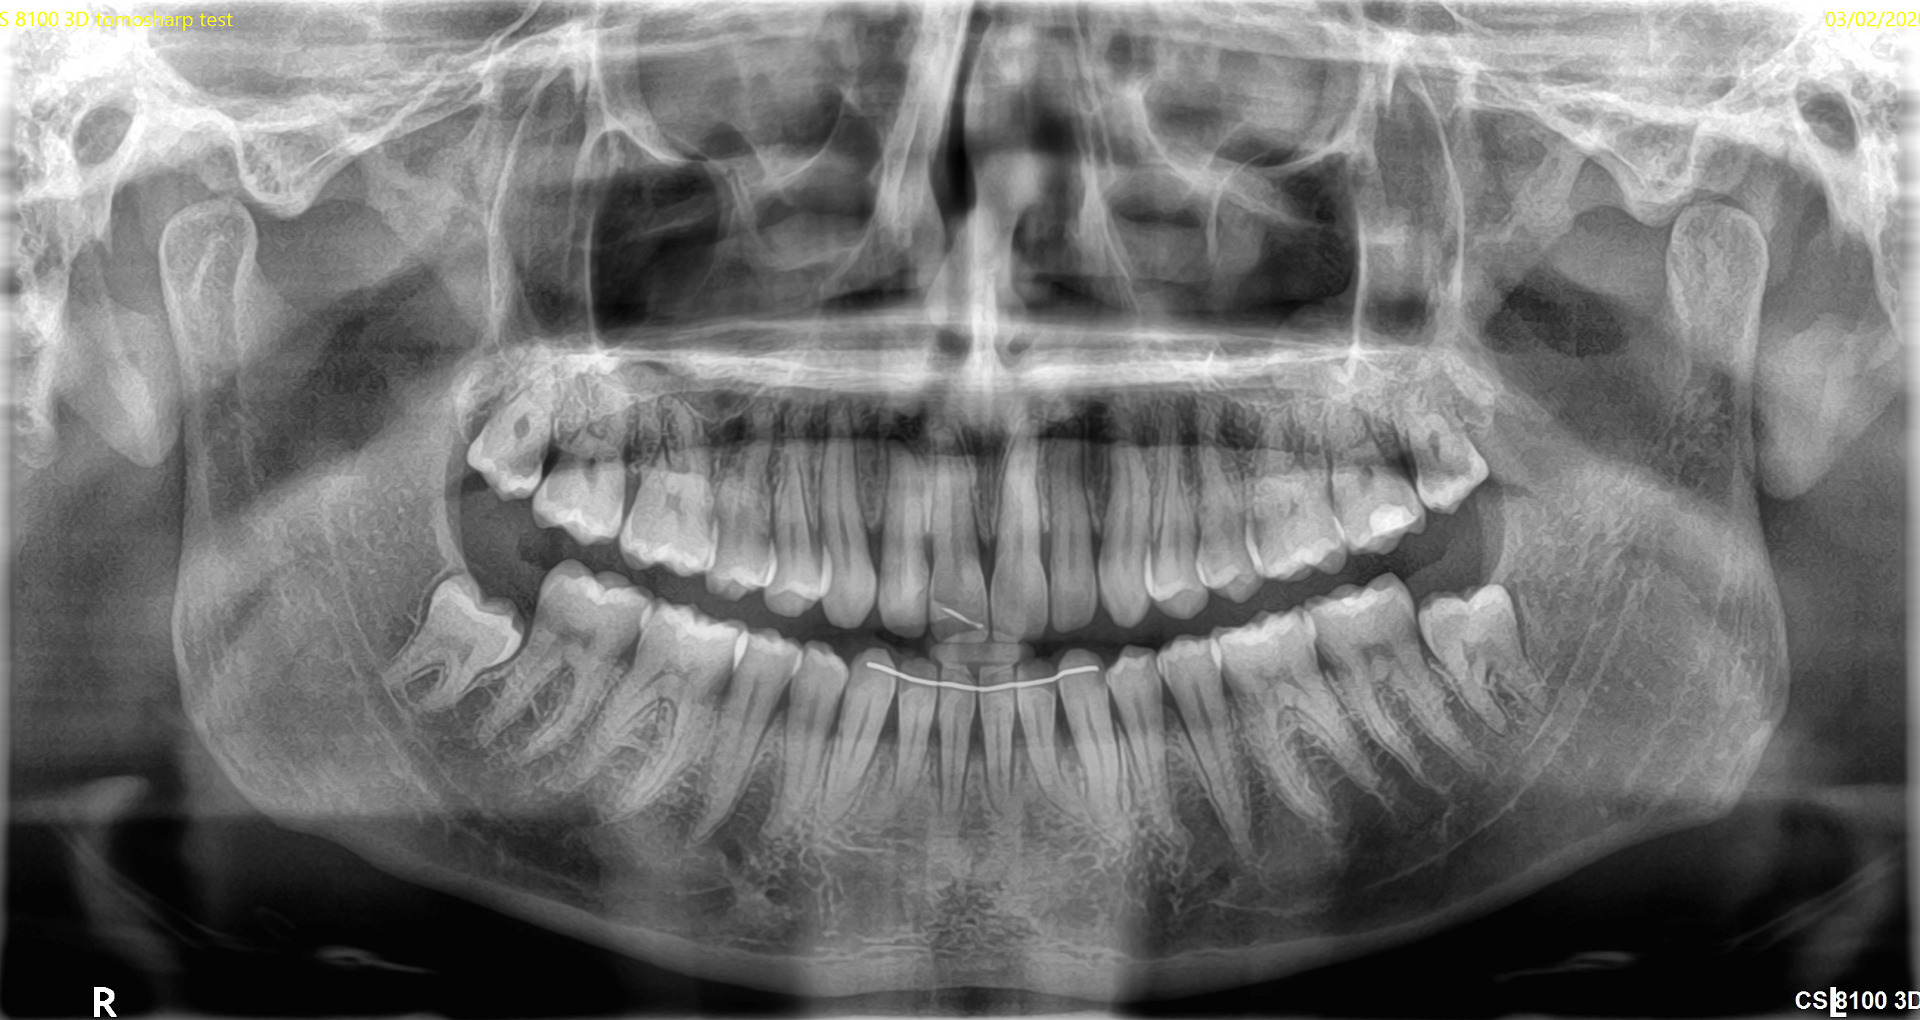

- 3D-сканирование и радиография обеспечивают детальные изображения зубов, челюстей и окружающих тканей;

- компьютерная томография (КТ) предоставляет трёхмерные изображения, необходимые для сложных процедур, таких как имплантация или лечение корневых каналов.

Наши специалисты применяют передовые технологии — трёхмерное сканирование, рентген, интраоральные камеры и компьютерную томографию для точного выявления всех проблем полости рта.